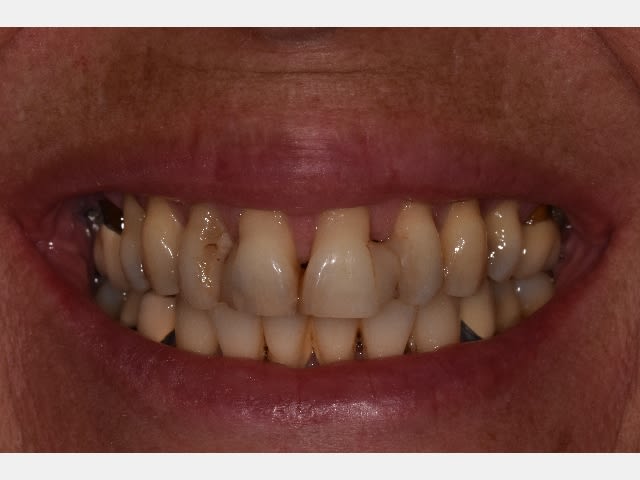

J'ai vu cette patiente de 60 ans ce matin et je sèche un peu sur le traitement, surtout par rapport aux récessions antérieures, elle a surtout une demande esthétique au niveau de la zone antérieure maxillaire.

La parodontite est stabilisée pas de poches au sondage, mais la contention antérieure qui a été faite il y a 20 ans suite à un traitement ortho-paro vieillie mal.

Des avis? peut on gérer ce cas avec en recouvrant les récessions avec de la mucco gingivale et ensuite des recontitutions? ou alors fausse gencive céramique?

T’as pas lésion osseuse angulaire , sur les Canines notamment ? Et ça saigne pas en bas , sur ? Vas y mollo , ça m’a l’air stable du tout la paro , vu d’ici..

Même avis sur la paro qui semble limite. Par contre, un joli bridge de contention 3-3 en zircone donnerait un joli résultat esthétique, la fausse gencive c'est rarement génial, sauf à créer des zones de rétention de plaque.

Point de vue morpho, 11 21 seront légèrement raccourcies, et la récession masquée de ce fait, et les embrasures seront facilement fermées...

Je suis d'accord pour le bridge ou des facettes mais oublie la fausse gencive c'est moche. Juste des dents un peu plus large et plus longues, fait un wax up et un essayage avec mockup. Pour moi les facettes avec minimum de délabrement seraient le mieux mais si des dents sont mobiles bridge qui servira de contention sera une solution acceptable.

Je veux bien me faire pendre si en M et D des incisives supérieures on a pas de poches.

Et si tu fais des couronnes, ça va lui faire des sacrés chicots hyper longs. À moins de bien lui raboter tout ça.

Et enfin y a un diastème de 5 mm entre 21 et 22. Ce qui veut dire que sur les futures couronnes il y aura des couronnes plus larges à gauche qu’ à droite.

À moins que tu te contentes de juste détartrer,d’enlever les tâches, et de juste refaire les compos à la bonne teinte.

la question était : la chir muco peut-elle permettre de recouvrir les récessions

les papilles sont bien conservées

Non elle ne peut pas, parce qu'une fois la paro traitée, les papilles seront à dache.

Tu as une alvéolyse périphérique de presque 50%, associée à des lésions infra osseuses, dont au moins une majeure en palatin de 12, tout cela n'étant masqué que parce que le biotype parodontal est favorable. Ce n'est pas grave, si le boulot est bien fait elle pourra le mener au bout, mais à moins d'avancées majeures en paro dont je n'ai pas eu connaissance, on ne fait pas encore repousser l'os, et quand on a de la gencive à 5mm au-dessus du niveau osseux, ça s'appelle une poche.